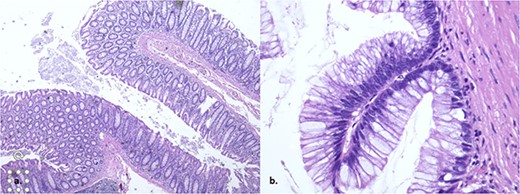

The pathology report unveils a confined low-grade appendiceal mucinous neoplasm with no rupture and clear margins (Fig. 3). The patient achieves a successful outcome with consistent monitoring and no complications following surgery.

The histopathology showed a low-grade appendiceal mucinous neoplasm with no rupture and clear margins.